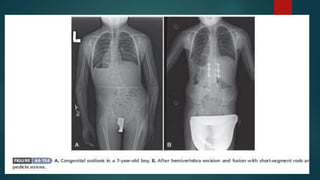

 HEMIVERTEBRA EXCISION:

 Hemivertebra excision can produce immediate correction of a congenital spine

deformity.

 This technique will remove the cause of and prevent further worsening of the

 Hemivertebra excision usually is reserved for patients with pelvic obliquity or with

fixed, lateral translation of the thorax that cannot be corrected by other means.

 At the lumbosacral area, excision of the hemivertebra can improve trunk

imbalance.